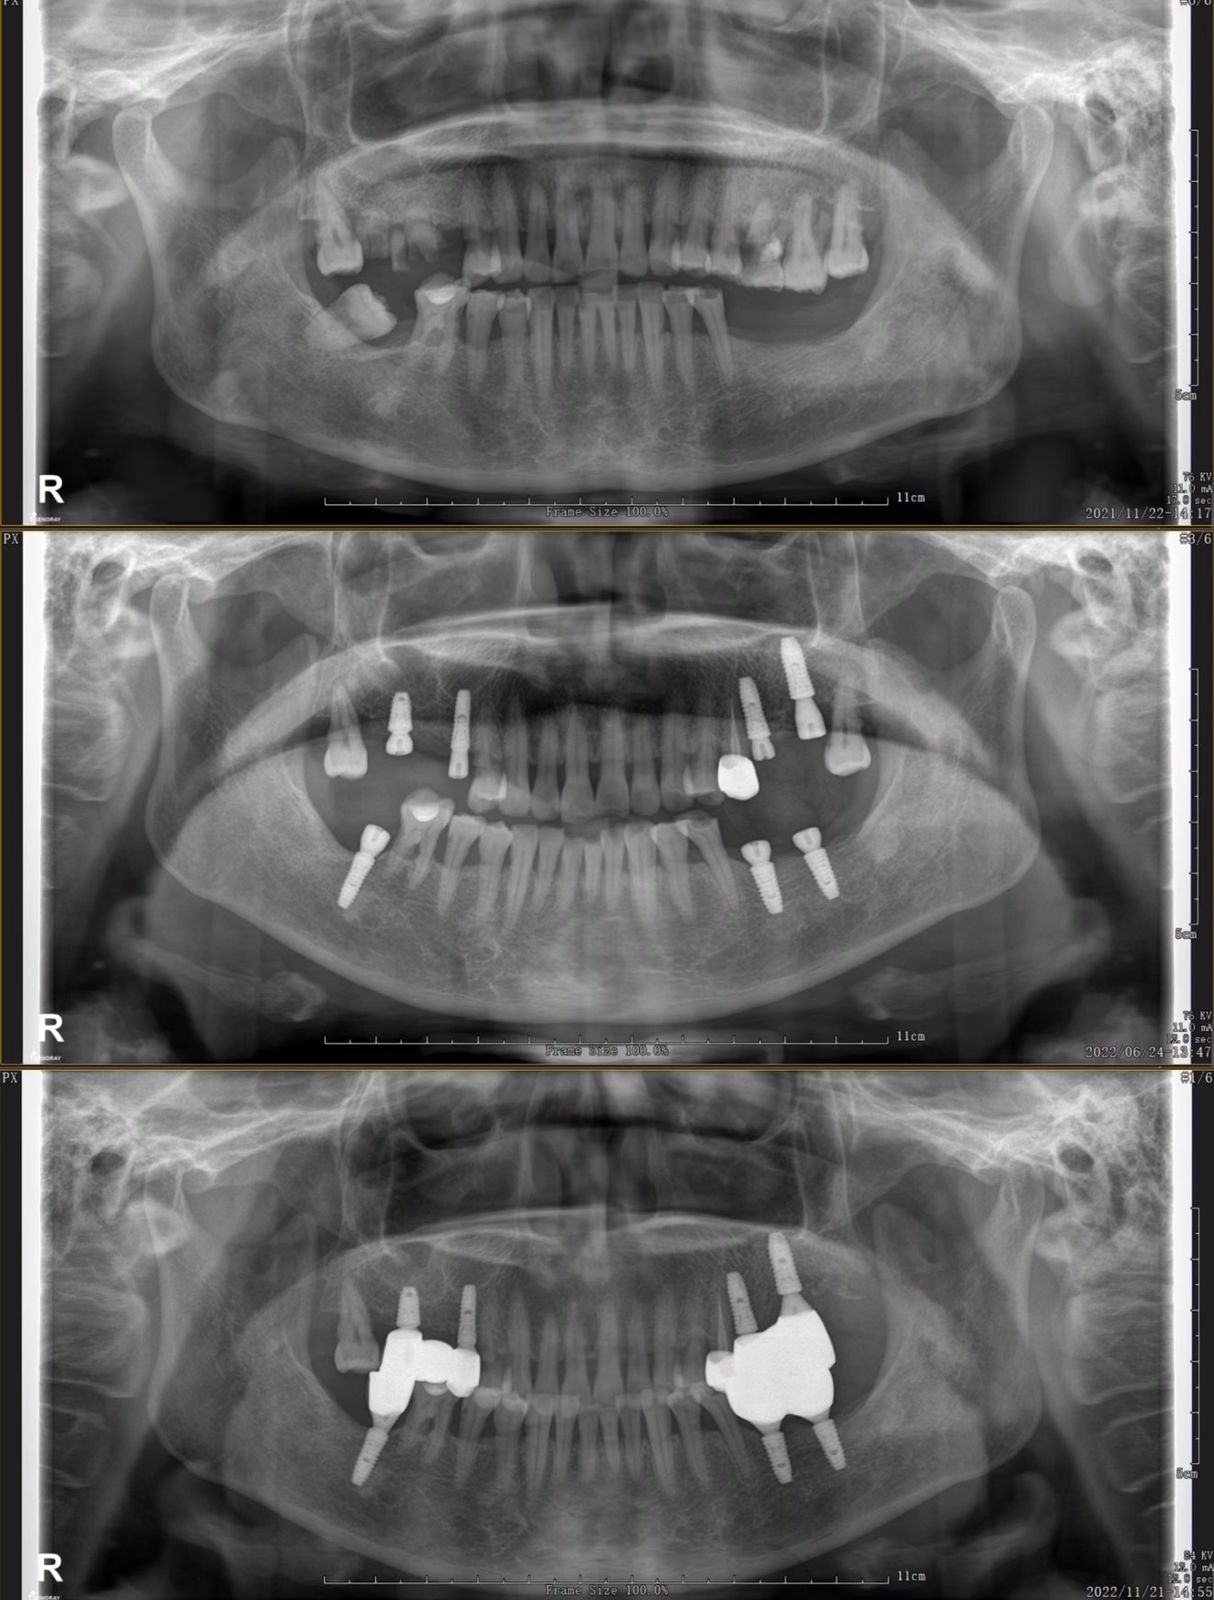

Примеры имплантации зубов в Хуньчуне

Имплантация зубов в Хуньчуне: описание и фото

Кому подходит: подходит для пациентов, у которых отсутствуют зубы по различным причинам.

Группы противопоказаний: пациенты с неконтролируемым воспалением пародонта, плохой гигиеной полости рта, выраженной костной резорбцией в области имплантата и т.д.

Продолжительность операции: обычно она занимает от 15 минут, зависит от количества и расположения зубных имплантатов.

Может дополнительно понадобиться: Наращивание кости. Если у пациента слишком давно отсутствуют зубы, это приводит к исчезновению костной массы, для этого доктор может проводить дополнительную операцию по наращиванию кости

Стоимость: От 30 000 рублей за имплант+абатмент+зубную коронку

Дентальная имплантация — это способ восстановить утраченные зубы с помощью искусственной опоры, которая устанавливается в костную ткань челюсти и служит основанием для будущего протеза. Конструкция обычно состоит из двух элементов: имплантата (аналог корня), который фиксируется в кости и обеспечивает надёжную поддержку, и коронки (видимая часть), которая возвращает зубу форму и полноценную жевательную функцию.